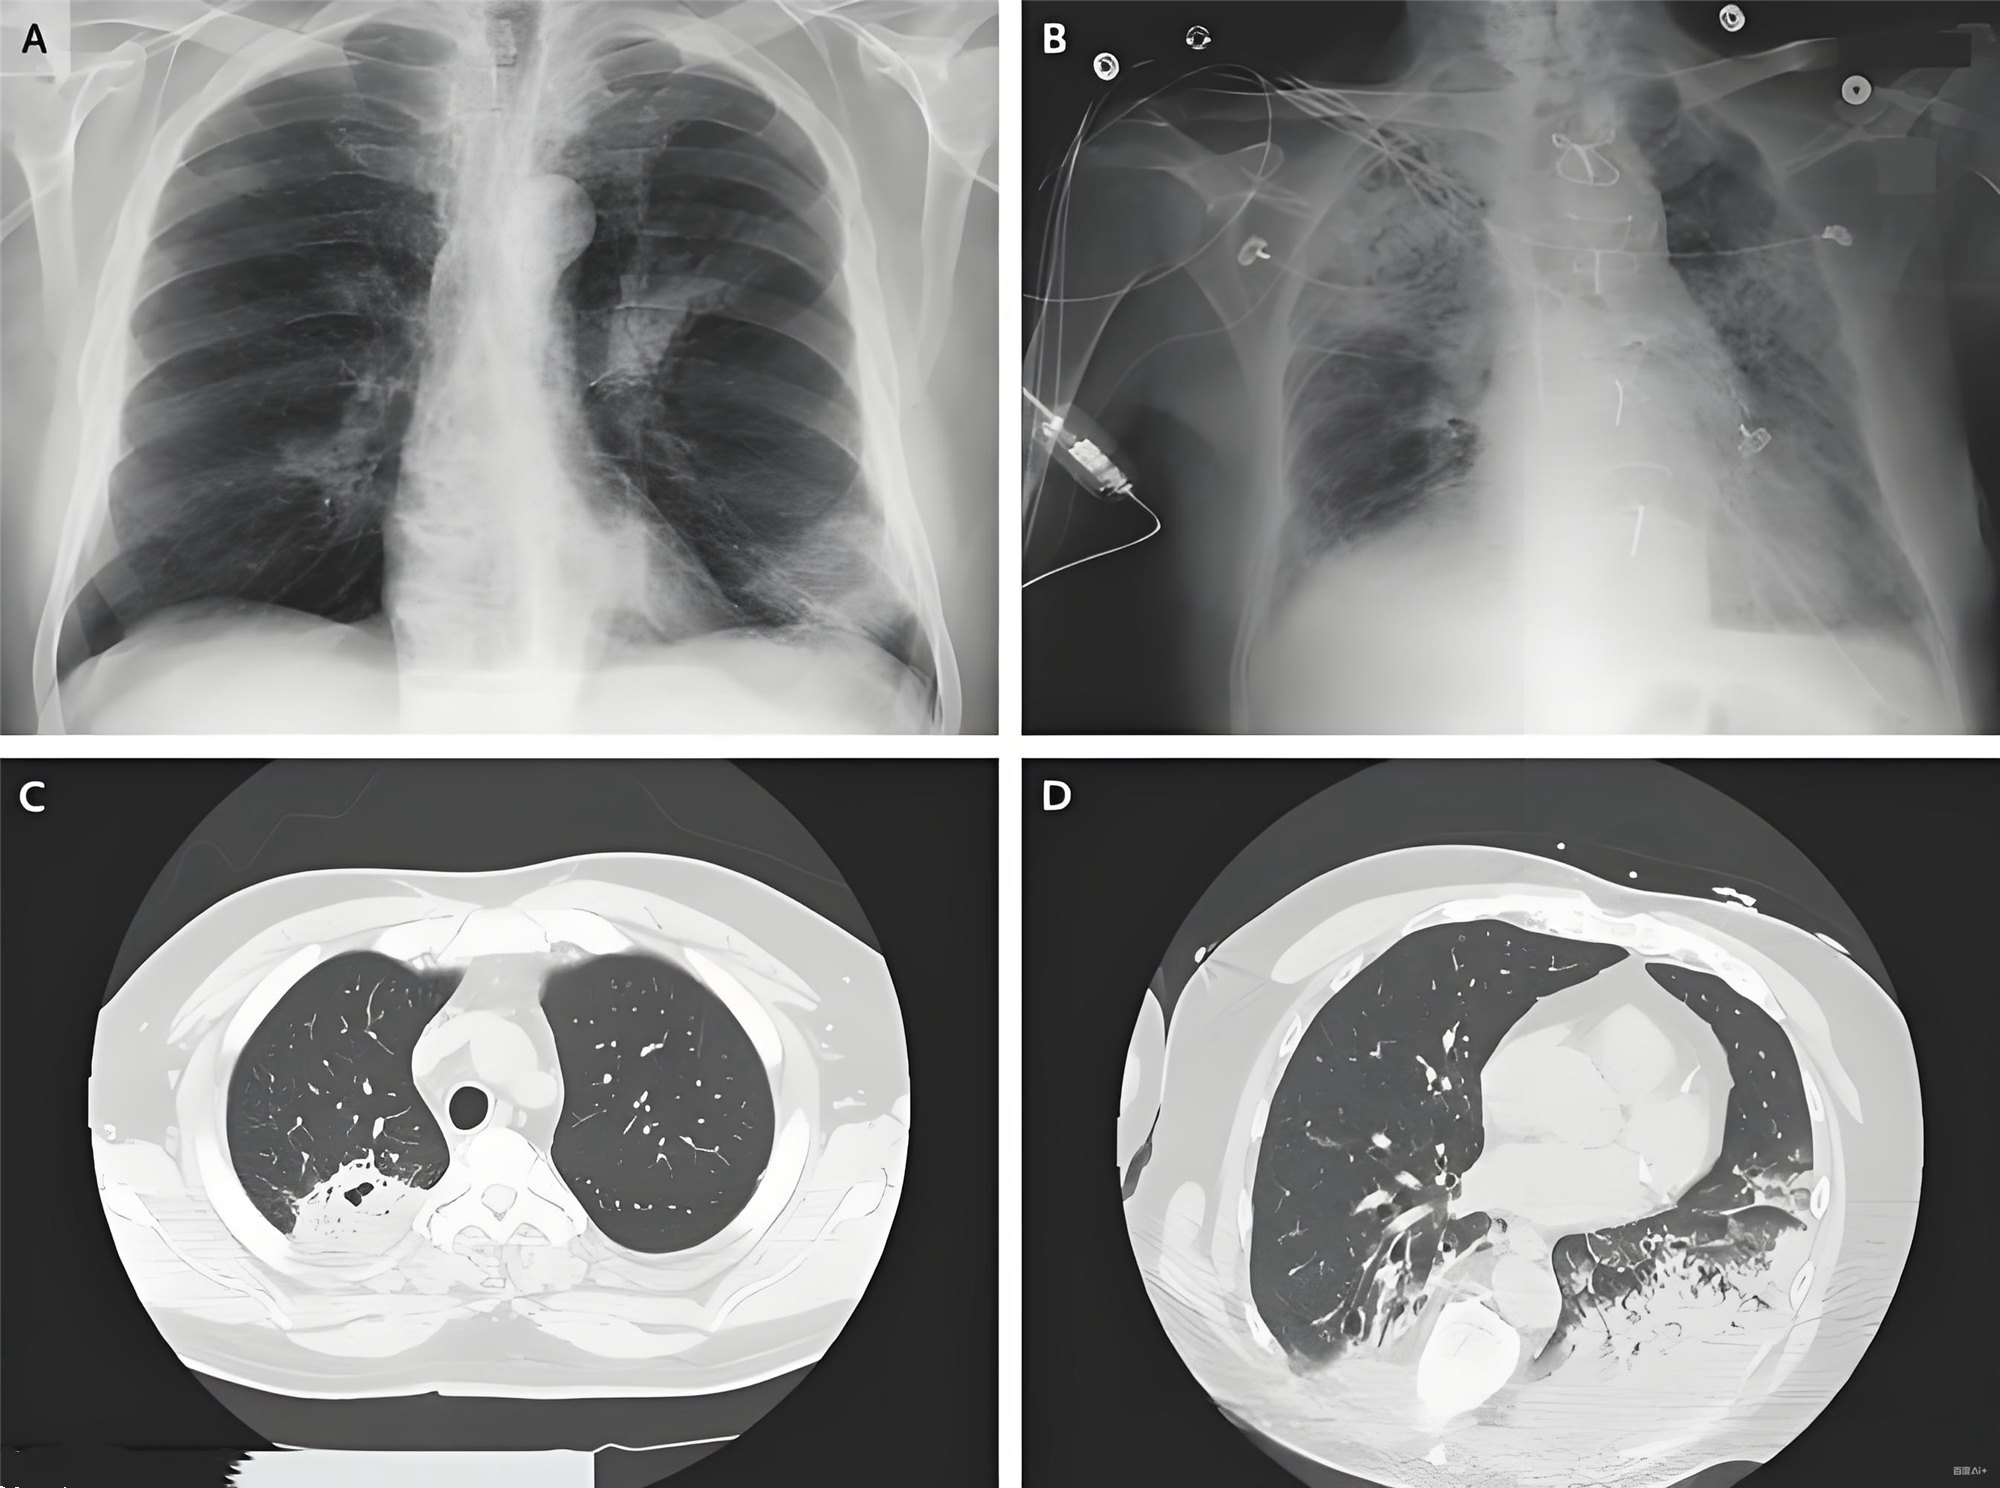

- 胸部CT示右下肺实变伴支气管充气征

- 影像学:右下肺实变(典型吸入性肺炎定位)